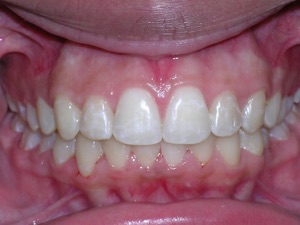

In this case, a young woman came to us with a desire to straighten her teeth. We elected to do Invisalign treatment with some enamel reduction and some dental arch expansion. Take a look...

Here she is on the day of appliance removal. You can see how the crossbite on the right has improved, as well as the lower front teeth crowding. Note that we elected to leave the lower second premolar in it’s rotated form.